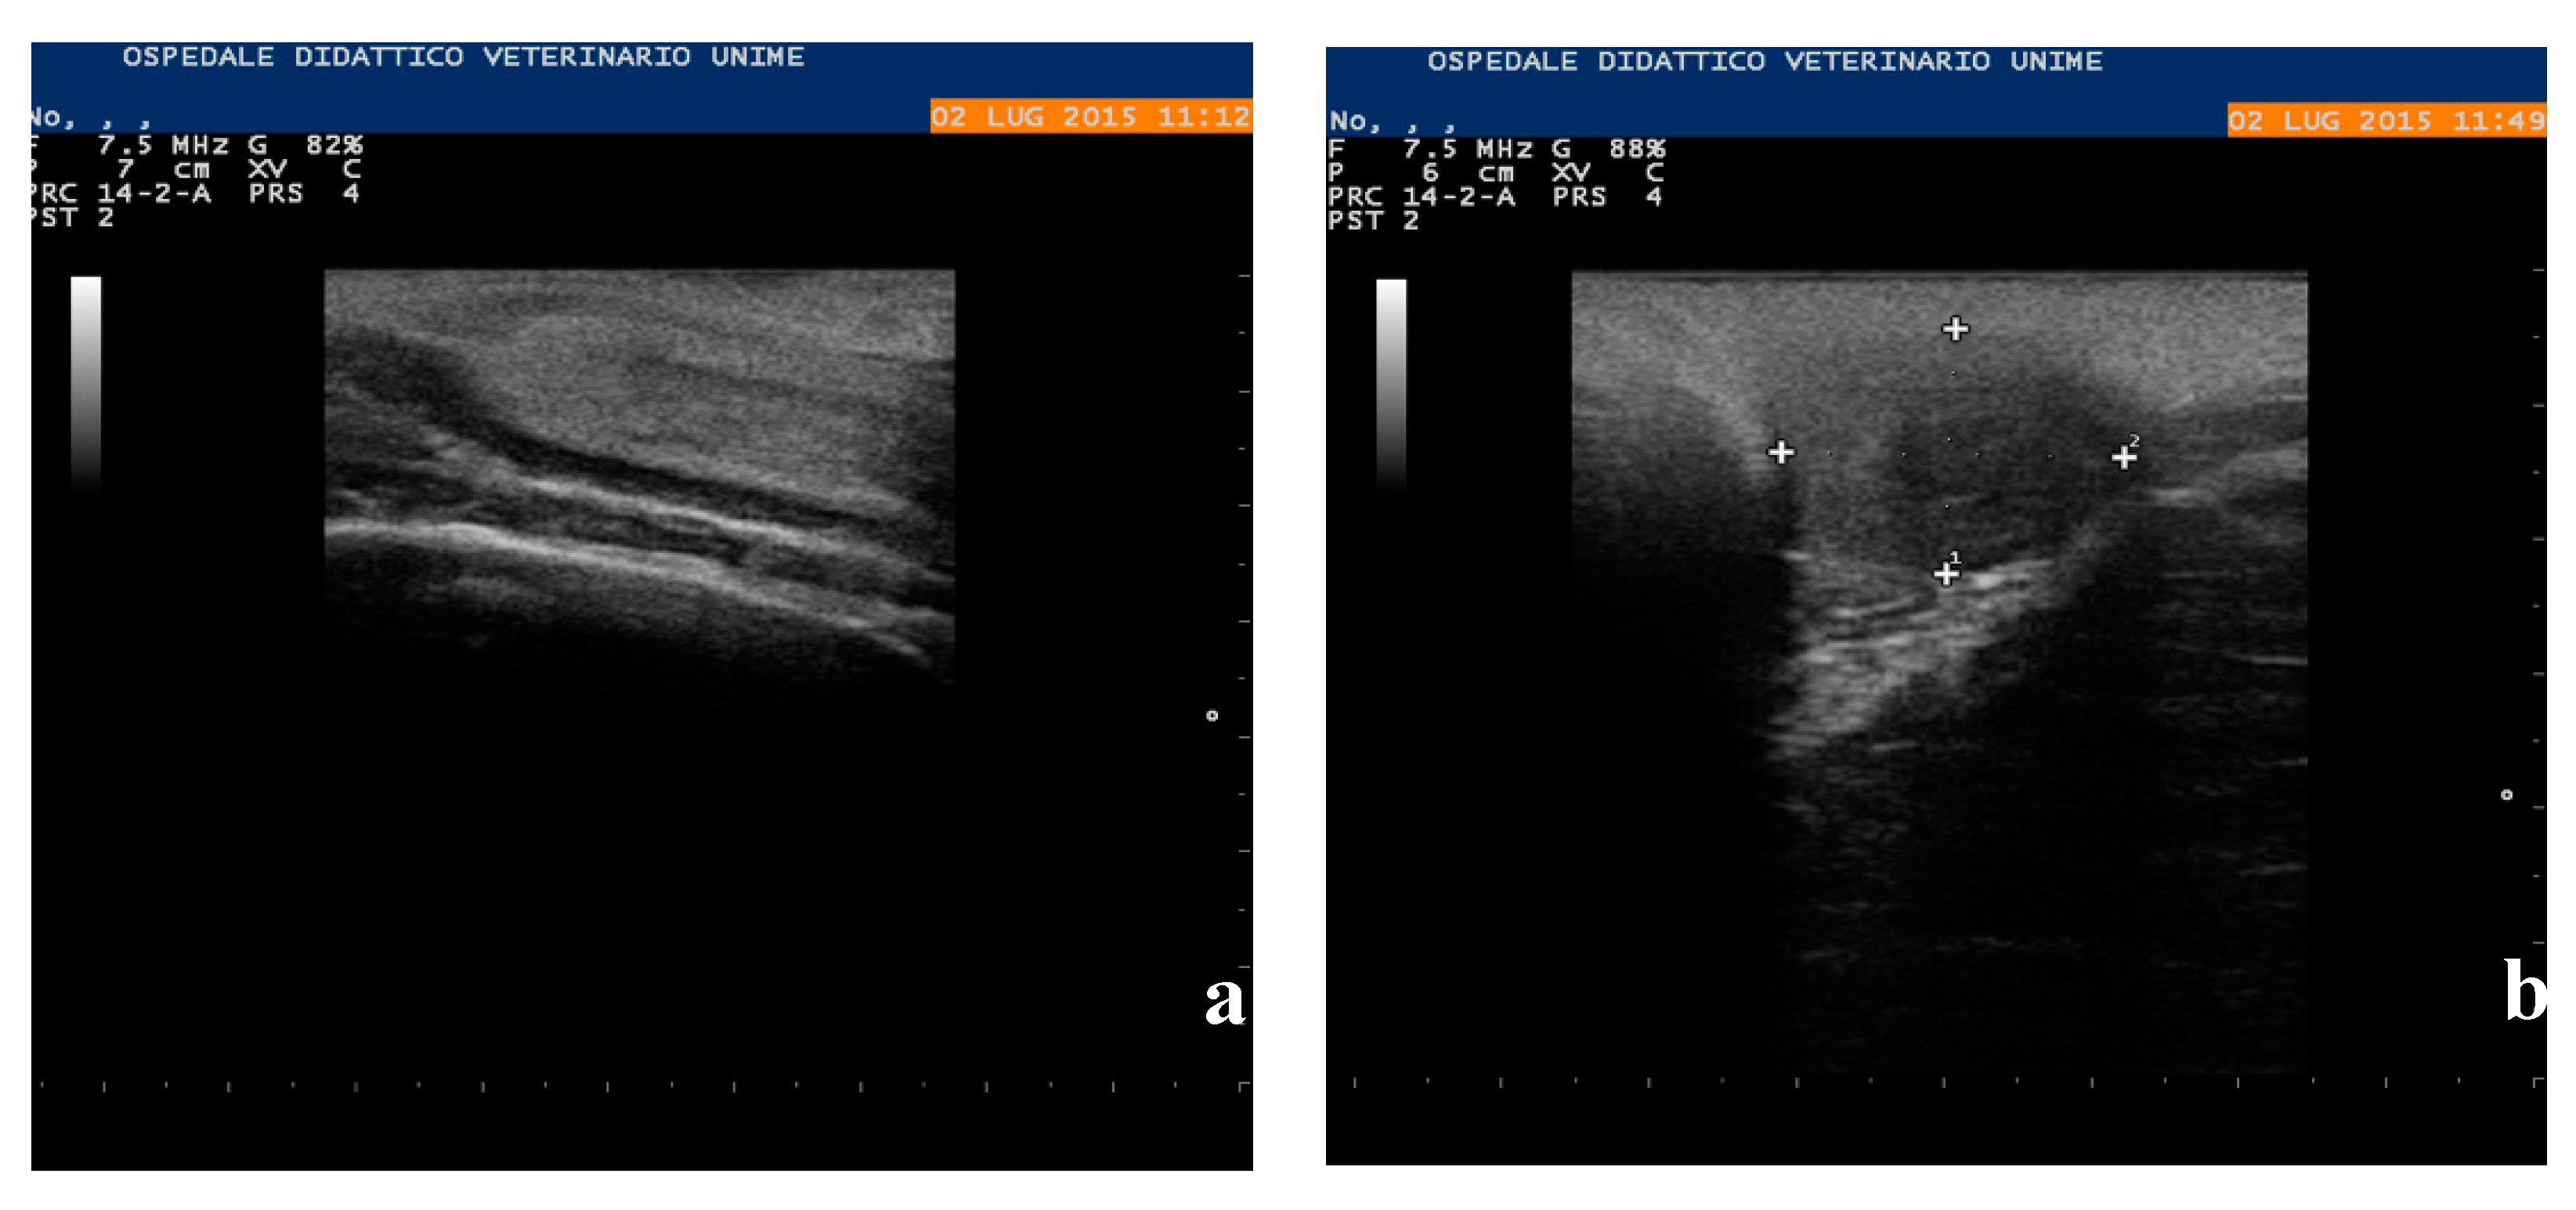

1. Introduction

2.2. Clinical Examination

3.3. Necropsy and Anatomopathological Examination